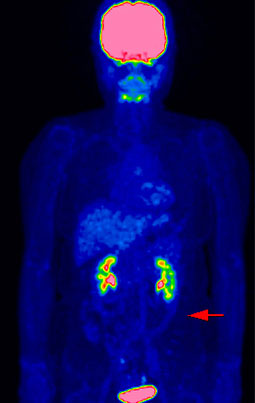

▲早期右乳癌